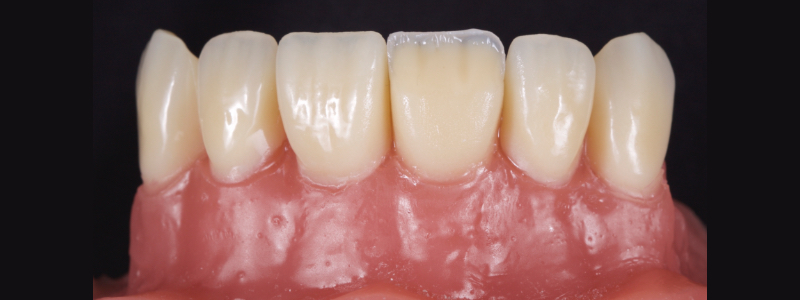

The chromatic enamels are built to full contour in the gingival and mid thirds but are under contoured in the incisal third (Figs. 18 and 19).

The next phase in the build-up is the application of a blue-grey resin mass in between the mamelon effects to create opalescence (Fig. 20). This should be sparing and confined to the incisal 2-3.0 mm. This layer should also be under contoured.

The final layering phase involves applying an achromatic enamel to the incisal third on the facial surface. This is adapted and smoothed with a flat plastic and a #3 brush/modeling resin (Figs. 21 and 22). The restoration is then polished.